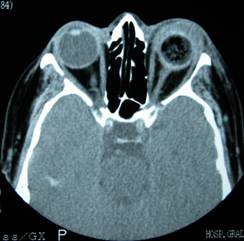

CT scan in which the prosthesis is observed as a dark field. Right orbital prosthesis